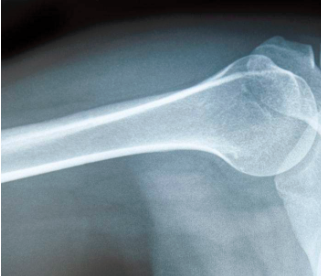

明明追问道:“骨头是不是白色的呢?”妈妈回答道:“对,所以骨折或者骨质增生的辅助检查,首选X光。”

“那CT又是什么呢?”“CT检查其实也是用X光给身体拍照片。不过,X光只是拍一张照片,而CT是在X光一层一层穿过身体后,从上到下拍多张照片,所以成像更加清晰准确,从某种意义上可以说是X光检查的加强版,不过,它的辐射也大于X光。”